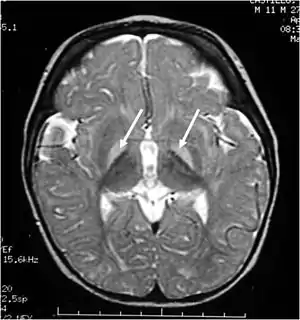

| ام آر آی از سر، گانگلیونهای بازال دچار آسیب هستند | |